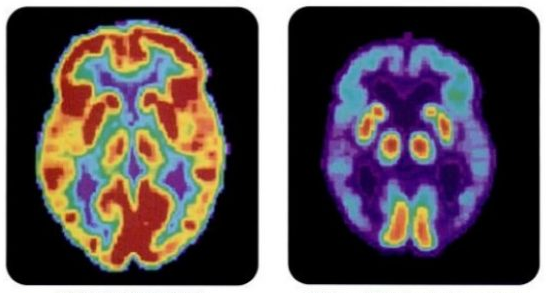

Aducanumab virker ved at fjerne det såkaldte ß-amyloid, et protein, som aflejres mellem hjernecellerne, og som anses for at være toksisk for hjernen (se GUIDEN65 artikel nedenfor). Der er andre mekanismer involveret i udviklingen af demens, men fjernelsen af amyloider er en af de vigtigste.